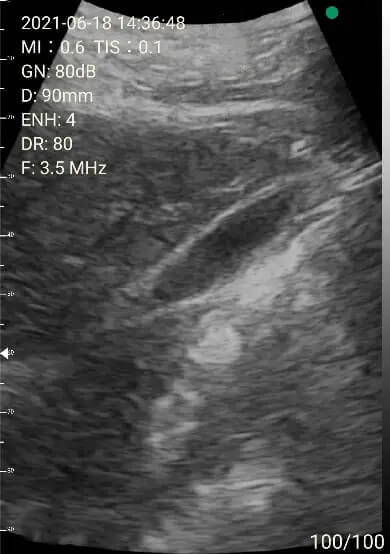

2. Abdomen review

Left lobe of liver

Portal area

Right lobe of liver

Images of thyoid scan on a 35-year-old healthy man.